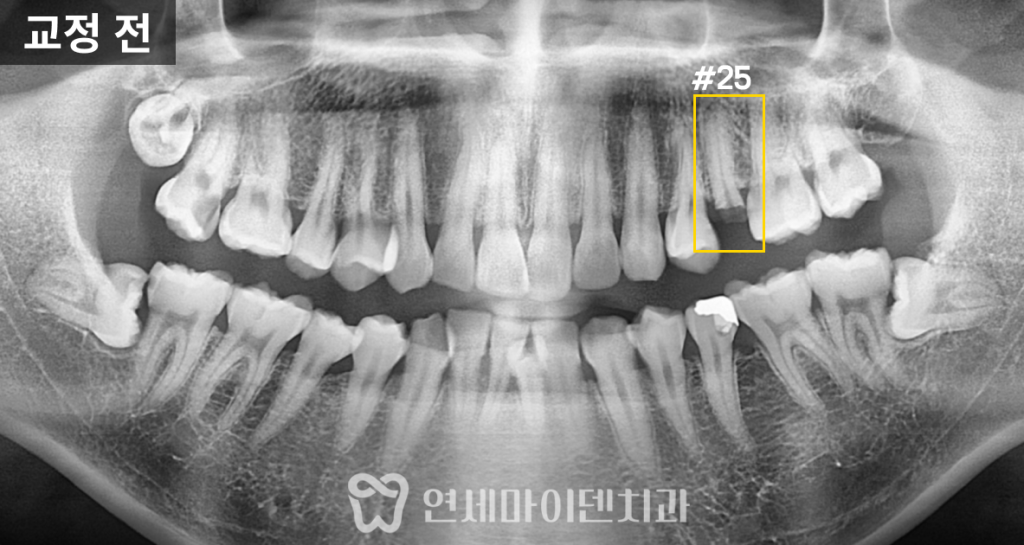

초진 파노라마 방사선 사진을 살펴보니,

왼쪽 위 작은 어금니는 머리 부분이 거의 소실되고 뿌리만 남아 있었습니다.

또, 사랑니가 세 개나 있어 전체적으로 공간이 부족했습니다.

환자분은 부정교합 개선깨진 어금니 복원을 동시에 원하셨기 때문에

교정과와 보존과가 협진하여 치료 계획을 세웠습니다.

비발치 교정치료 계획

전체 교합 사진을 보면 어금니의 맞물림은 비교적 양호했으나,

전치부의 배열 불규칙이 심했습니다.

특히 앞으로 많이 돌출된 아래 앞니는 발치를 고려해야 할 정도였지만,

발치를 진행하면 잇몸이 더 소실되면서

블랙 트라이앵글이 심해질 위험이 컸습니다.

이러한 이유로 하악 전치부 발치는 피하고,

사랑니 세 개를 발치하여 필요한 공간을 확보한 후

비발치 교정으로 치열을 개선하기로 결정했습니다.